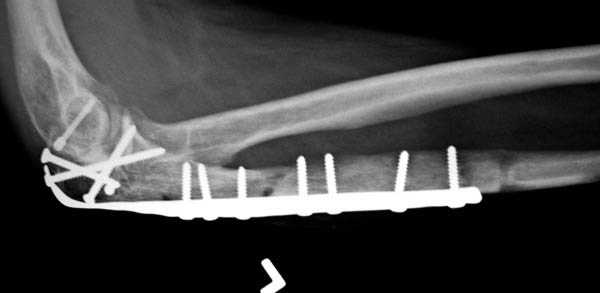

Здесь выставлены несколько случаев и варианты фиксации локтевого отростка, некоторые в комбинации с другими переломами.

перелом локтевого отростка с переломом головки лучевой кости (использованы 2 мм шурупы)

3 вариант

перелом с capitelum humerus и проксимальной трети улна